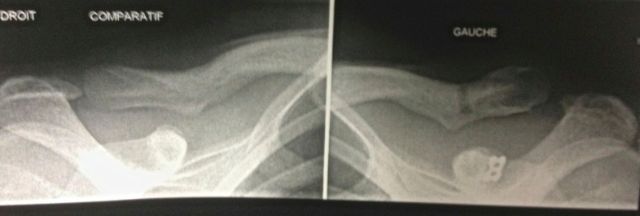

Contrôle radio de la réduction d'une luxation acromio-claviculaire

Figure 3 : Contrôle radio de la réduction d'une luxation acromio-claviculaire